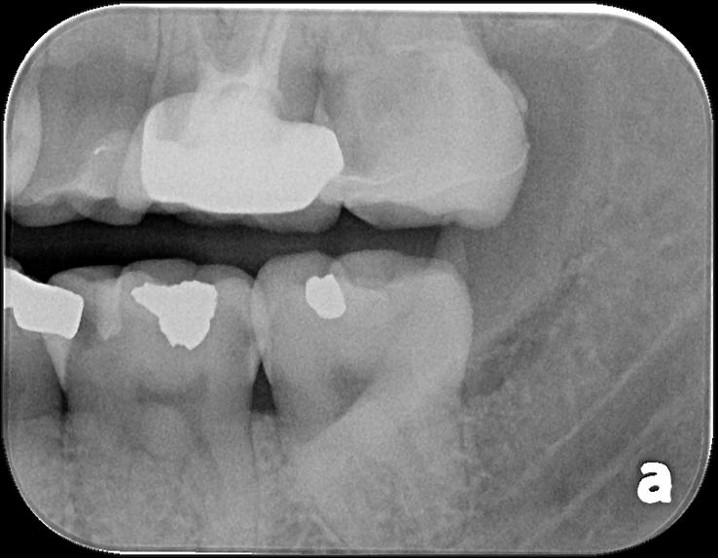

X光邊緣完整